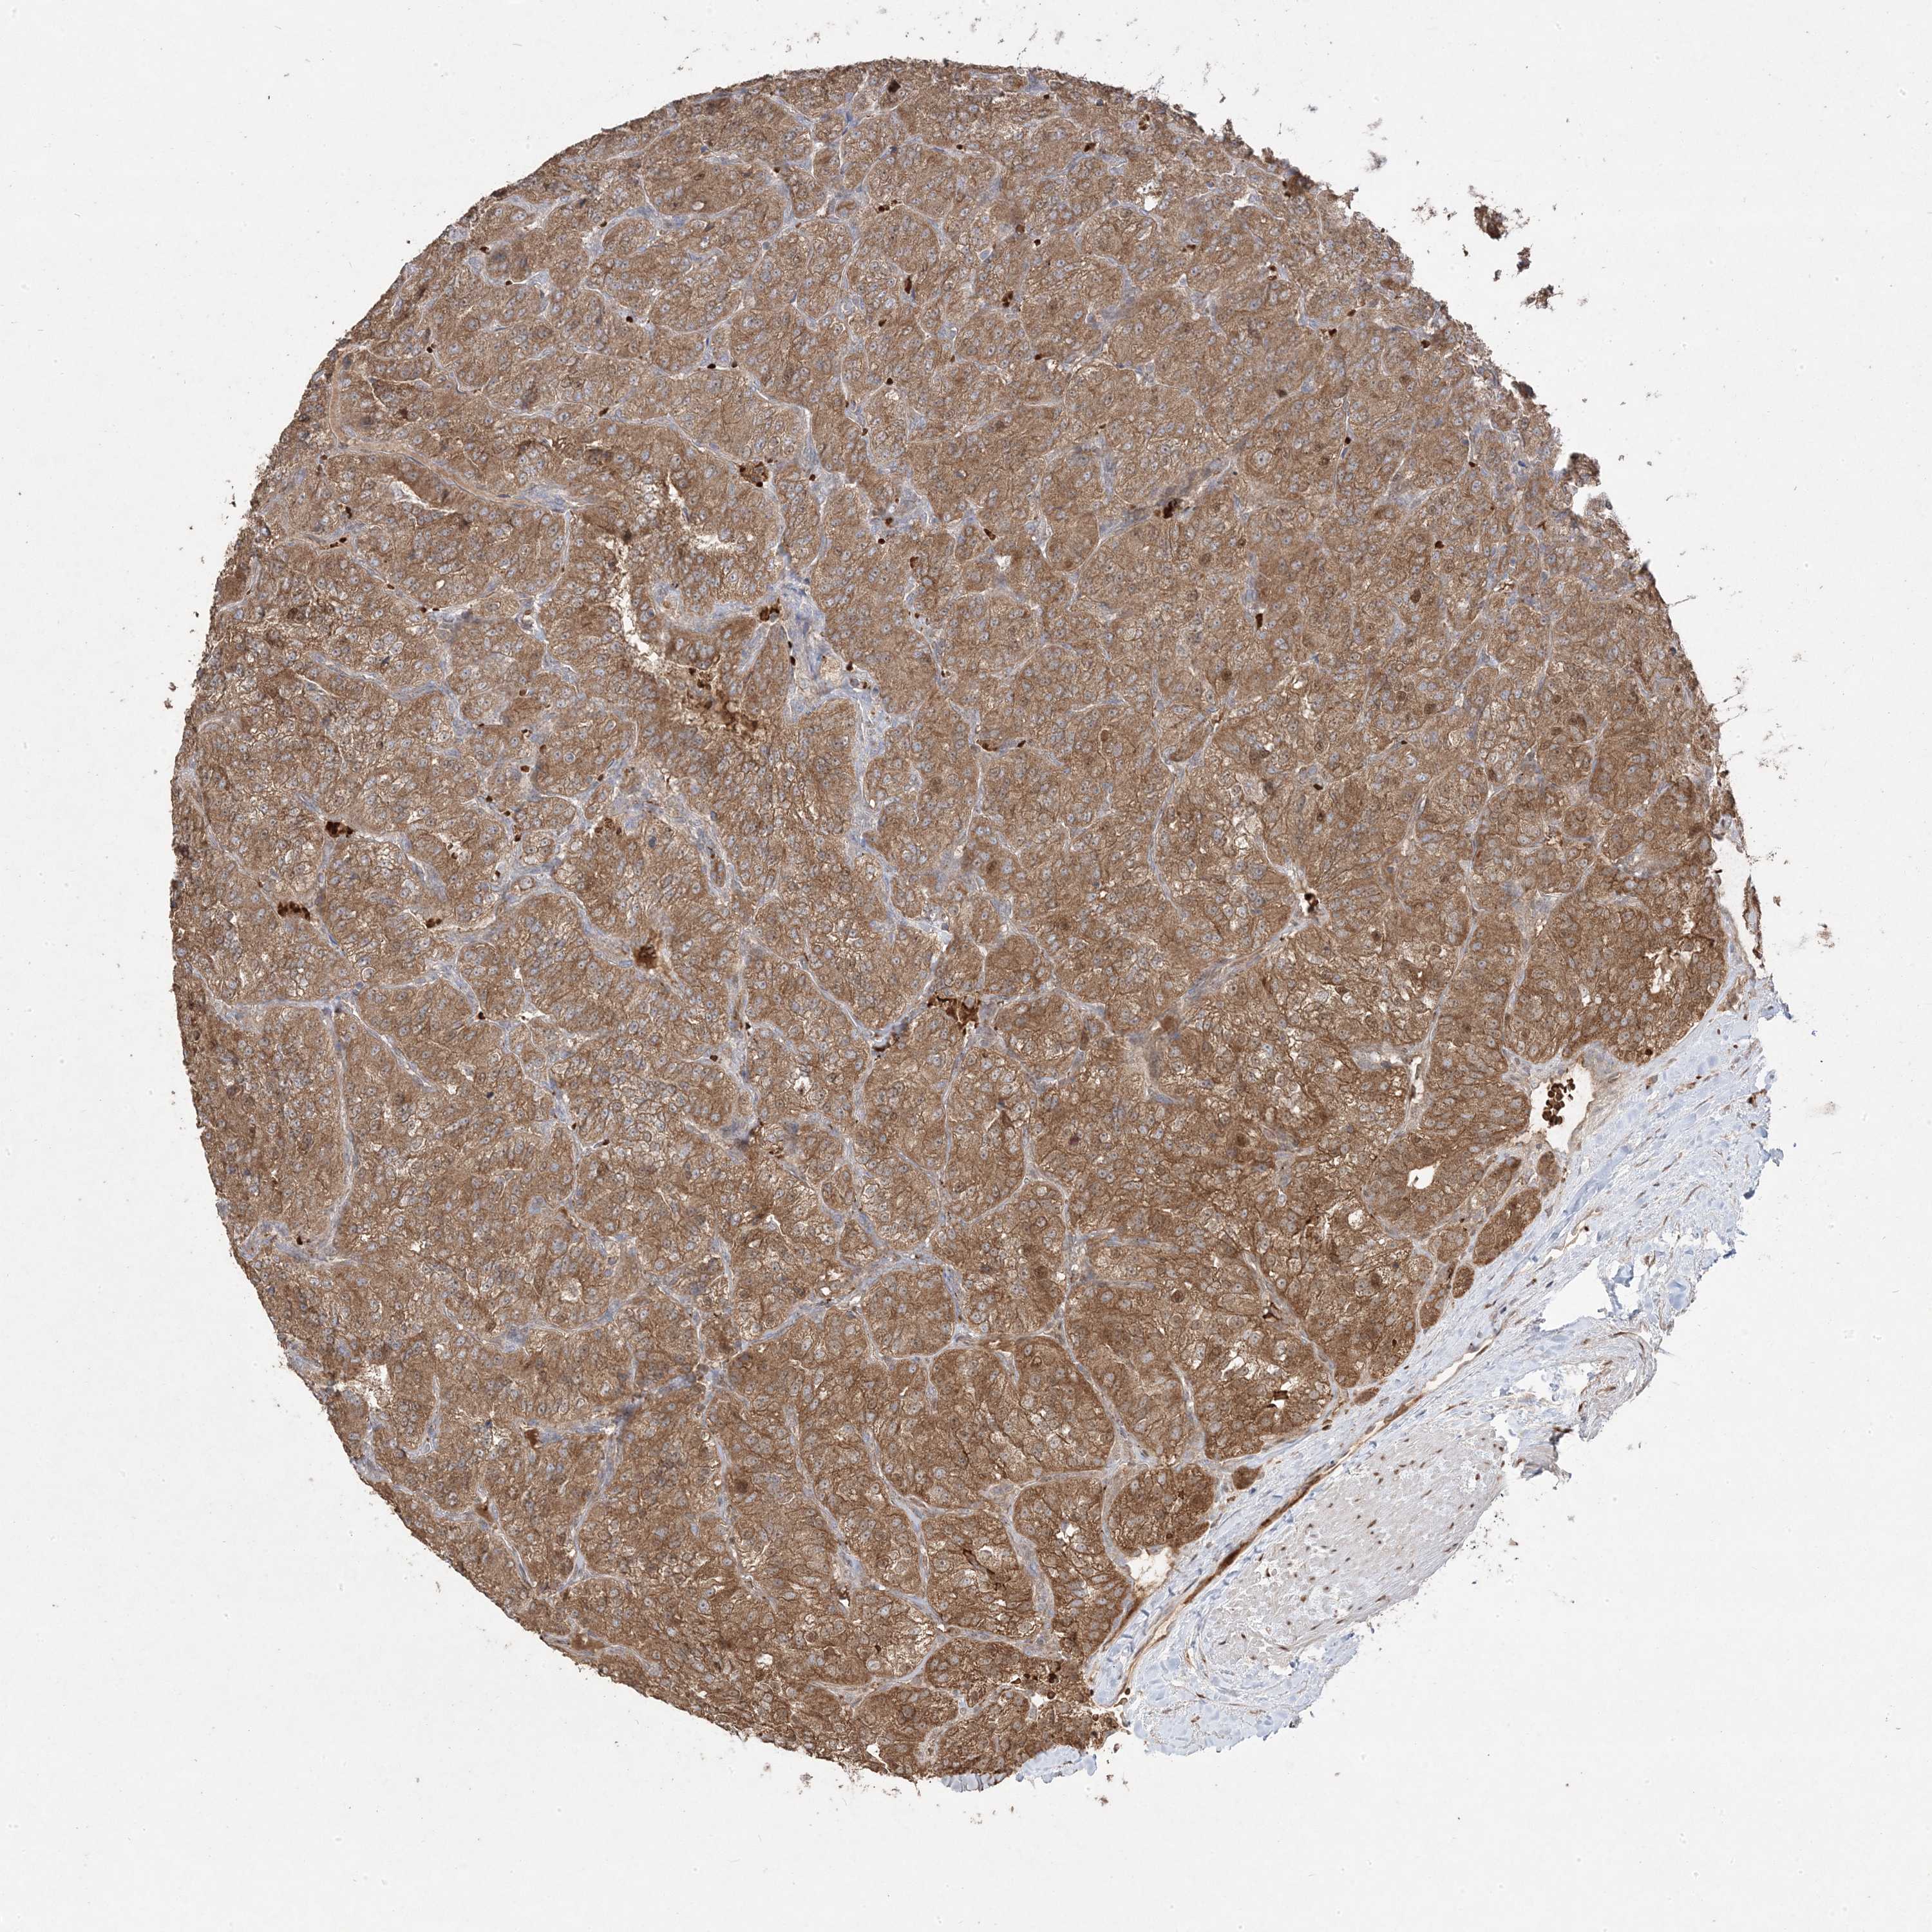

CANCER RENAL CANCER Show tissue menu

KICH TCGA KIRC TCGA KIRC VALIDATION KIRP TCGA PROTEIN RCC CPTAC PROTEIN EXPRESSION